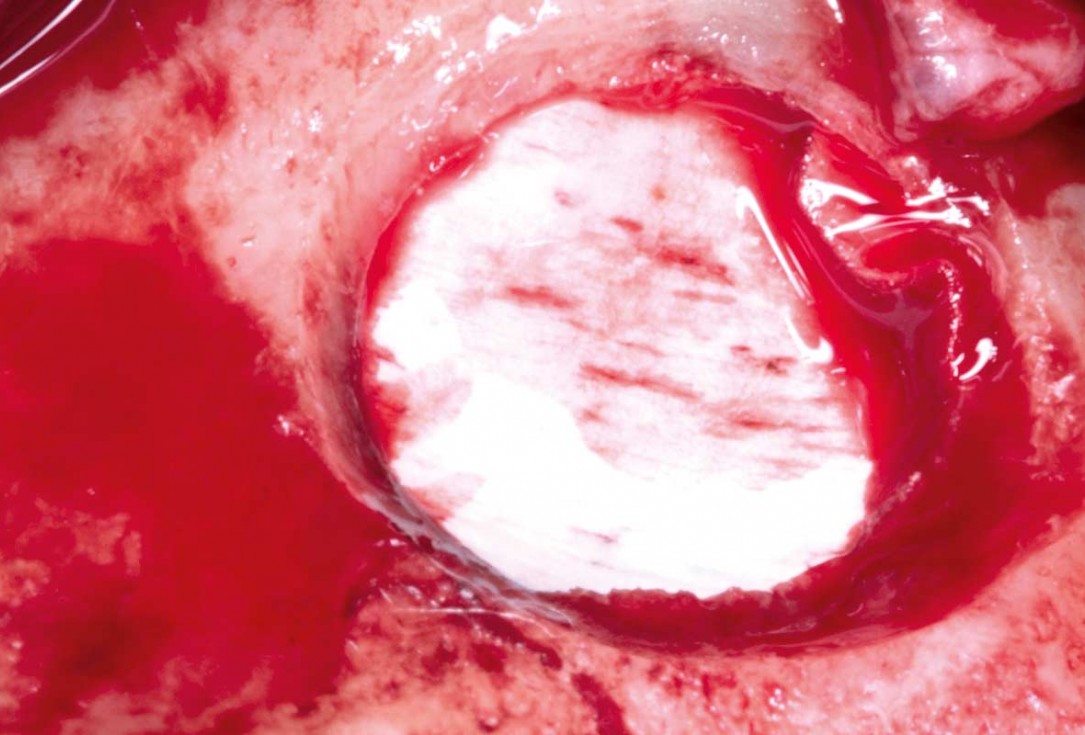

04/35 - Preparation of the lateral sinus window using piezosurgeryMaxillary sinus cyst removal using the Crocodile Technique and subsequent lateral sinus lift - Dres. C. Scognamiglio and A. Perucchi